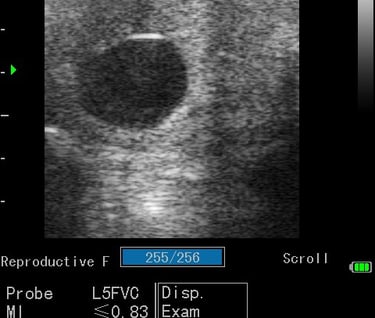

Gynécologie